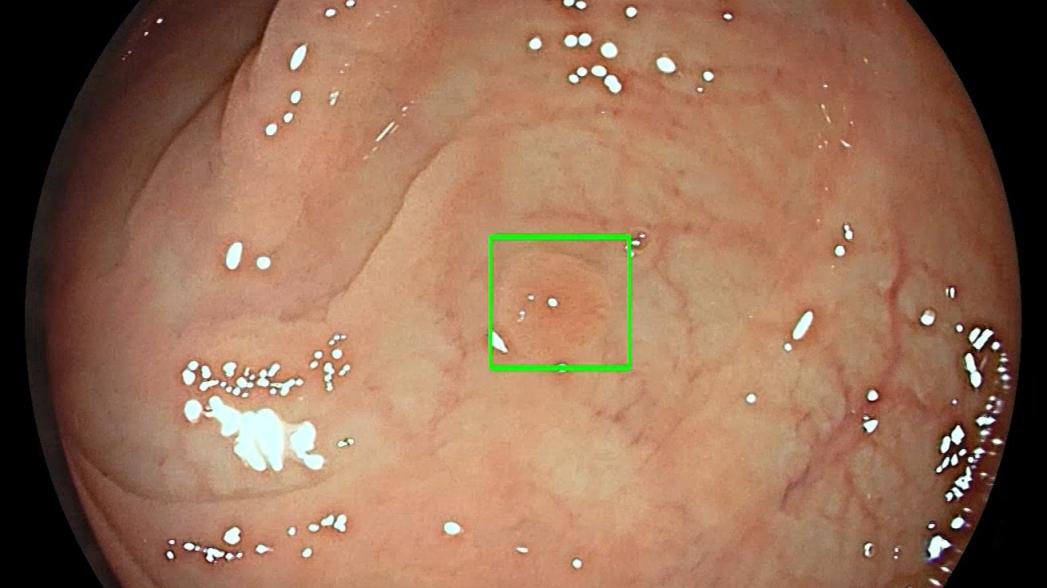

Модуль GI Genius использует программное обеспечение на основе алгоритмов искусственного интеллекта, чтобы в реальном времени обнаруживать наличие предраковых поражений и выделять их визуальным маркером, выступая в качестве внимательного "второго наблюдателя". Модуль GI Genius автоматически обнаруживает полипы, в том числе небольшие плоские полипы, которые могут остаться незамеченными, что повышает точность и снижает риск возникновения раковых заболеваний между процедурами колоноскопии.